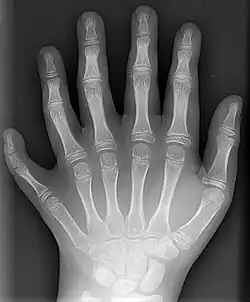

![]() Rentgenový snímek levé ruky desetiletého chlapce se šestiprstostí | |

Polydaktylie je vlastnost určená evoluční fází čtyřnožců, kdy se při přeměně ploutví v končetiny vyvinulo více než dnes běžných pět prstů. Z hlediska soudobé humánní a veterinární medicíny jde o souhrnné označení vrozené vady, jež má za následek větší počet prstů na noze či ruce než je běžné. Často bývá tato vada dědičná. Vyskytuje se velmi často u dětí s Patauovým syndromem. Nejběžnější formou polydaktylie u lidí je šestiprstost.